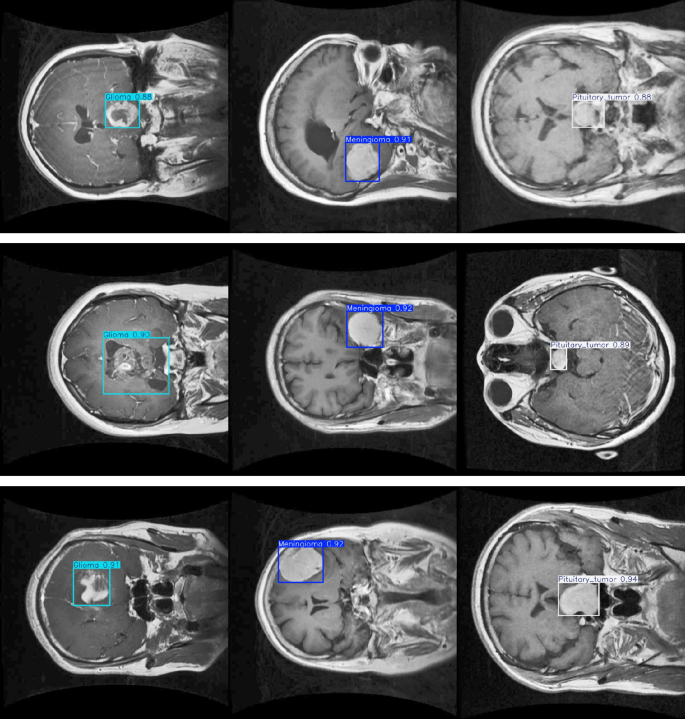

The study originally used only a single dataset from the Kaggle platform, which could indeed limit the model’s generalization ability and clinical applicability. Therefore, to enhance the model’s performance across different data sources, we introduced a brain CT image dataset from Radiopaedia (https://radiopaedia.org/search?scope=cases&sort=date_of_publication.) for tumor detection tasks. This dataset includes brain CT scan images from various patients, covering different types of tumors such as gliomas, meningiomas, and pituitary tumors.

Figure 12 shows multiple brain CT scan images from the dataset, with bounding boxes highlighting different types of brain tumors, accompanied by predicted class labels and confidence scores. The confidence score next to each bounding box reflects the model’s confidence in its prediction. Higher confidence values (e.g., 0.92 for meningioma) indicate greater certainty in the tumor type identification. This dataset not only helps evaluate the model’s accuracy in recognizing and localizing brain tumors but also serves as a benchmark for validating tumor detection models in other datasets, enhancing the model’s clinical relevance and generalization ability. By validating across different datasets, we can more comprehensively assess the model’s adaptability in diverse clinical settings, further strengthening its reliability and effectiveness in real-world clinical applications.